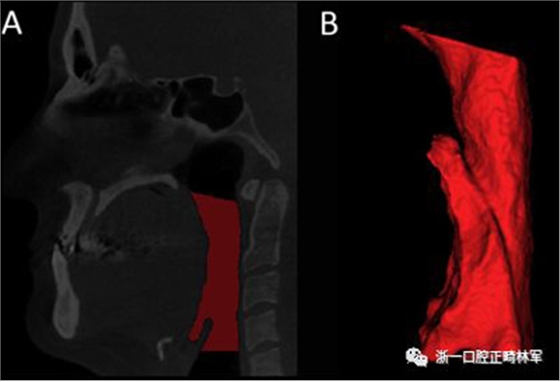

咽腔體積(PS體積)的分析是從三維模型進(jìn)行的。三維模型的重建采用軟件Insight ITK-SNAP(版本2.4.0; Cognitica,Philadelphia,Pa)的半自動分割模式建立,該模型以立方毫米測量結(jié)構(gòu)的體積。本研究中測量的體積對應(yīng)于口咽和下咽部之間的聯(lián)合。為此,我們按照Park等描述的解剖學(xué)定義確定了從后鼻棘到第一頸椎的最低點的上部參考線,以及在垂直于內(nèi)側(cè)矢狀面的第四頸椎最低點上描繪的下部參考線(圖5)。

圖5.A,使用文本中描述的參考點對咽腔進(jìn)行分割(紅色); B,口咽和下咽部之間的聯(lián)合體積。